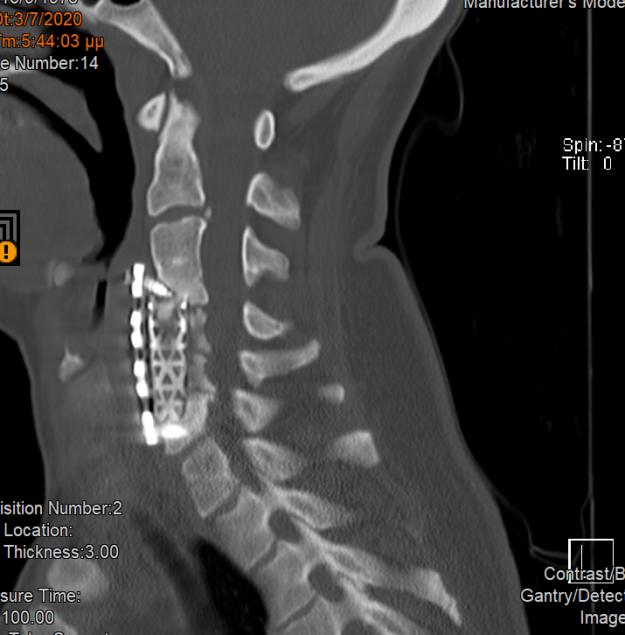

Νεαρή ασθενής 17 ετών με εκτεταμένη συριγγομυελία από την αυχενοπρομηκική συμβολή έως το τελικό τμήμα του νωτιαίου μυελού, λόγω συνδρόμου Chiari. Κλινικά αιμωδίες (μουδιάσματα) άνω άκρων, ζάλη. Αφού ο εργαστηριακός έλεγχος απέκλεισε συνοδά προβλήματα (πχ καθηλωμένο τελικό νημάτιο κ.α.) αποφασίστηκε η επέμβαση αποσυμφόρησης του οπισθίου κρανιακού βόθρου με ανάδυση των αμυγδαλών της παρεγκεφαλίδας και μηνιγγοπλαστική.…